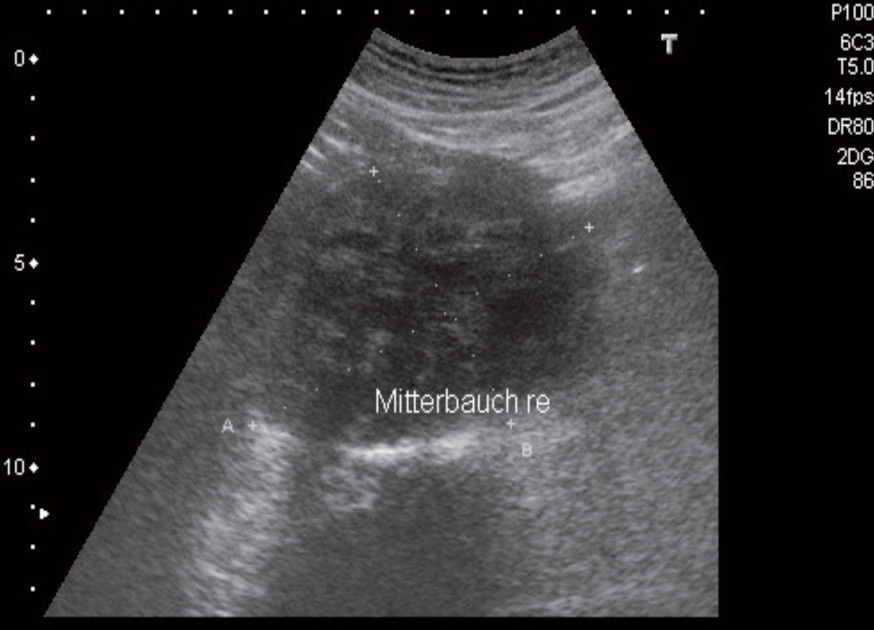

Die ebenso querschnittlich ausgebrachte Praxisausstattung (Abb. 2) ist diesem Umstand absolut angemessen. Moderne diagnostische und therapeutische Möglichkeiten versetzen den allgemeinmedizinisch tätigen Bundeswehrarzt in die Lage, die in der stationären Weiterbildungsphase erlernten Grundfähig- und fertigkeiten anzuwenden und unterfachärztlicher kollegialer Betreuung am Patienten auf Facharztniveau weiter zu entwickeln.